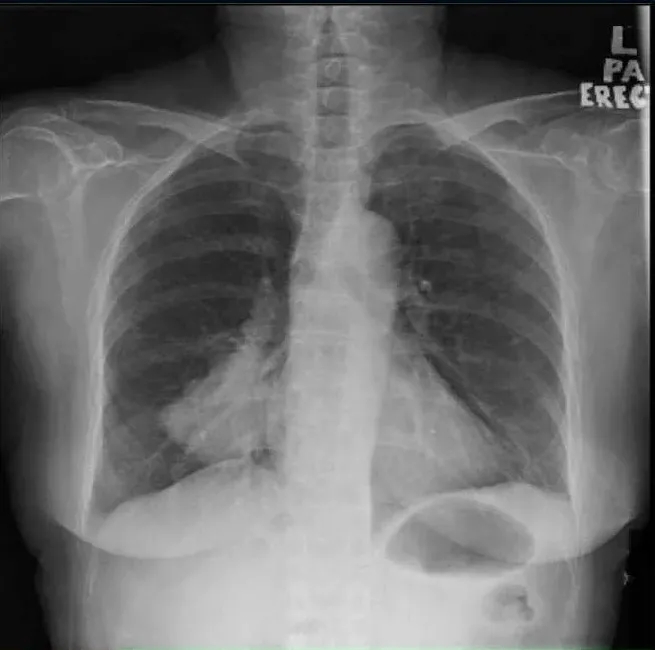

她第一次就诊时的常规胸片(图1)检查偶然发现了右肺肿块。随后的胸部增强计算机断层扫描(CT)(图2)显示肺右下叶后基底段的肺肿块大小为4.7×7.0×7.0 cm(前后×宽度×头尾)。肿块附近也有卫星结节。对肿瘤进行支气管镜活检,组织病理学检查(HPE)结果显示腺癌,证实为原发性肺恶性肿瘤,表皮生长因子受体(EGFR)基因的外显子19缺失。

图1. 胸部X线,右下肺叶有肿块